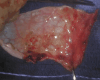

An 11-year-old boy presented in distress with tachypnea, holosystolic murmur, and a gallop. Echocardiography revealed mitral valve thickening and severe regurgitation. He required valve replacement with pathology consistent with acute on chronic valvulitis. This case underscores the importance of considering rheumatic heart disease, despite no preceding suspicious history.